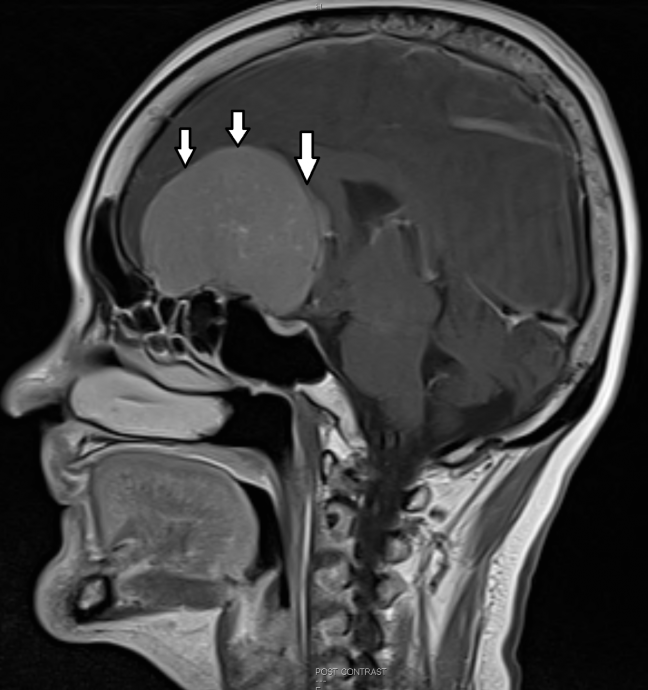

脑波检查时,脑神经内科医生发现龙妈妈的大脑机能出现障碍,于是转介到我的部门。做了电脑断层扫描后,才看到她的眼球后方颅底暗藏着一颗巨大的肿瘤,诊断为嗅沟脑膜瘤(Olfactory groove meningioma),由于体积太大(7x7x5cm),压迫前脑,造成颅内压增高,引发脑肿、反应迟缓、记忆退化等问题。